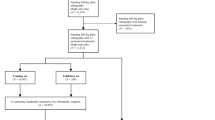

This multicenter retrospective study aimed to develop a deep learning-based algorithm to automatically measure patellar height parameters in lateral knee radiographs and evaluate its performance and generalization ability. We utilized a dataset containing X-ray images from three tertiary level A hospitals.

The images used in this study’s dataset were obtained from three tertiary A-grade comprehensive hospitals: The Second Affiliated Hospital of ** knees; and (4) unclear superior or inferior poles of the patellar or patellar ligament endpoints. The osteoarthritis criteria were used to include radiographs with clear patellar height markers. We retrospectively analyzed 3,923 knee joints, of which 2,341 met the inclusion criteria. A random selection of 90% of the cases from The Second Affiliated Hospital of ** to enhance the model’s robustness and generalization ability.